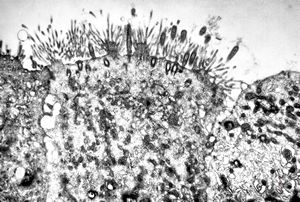

M,18y. | immotile cilia syndrome - bronchus - microvillous prominence

M,18y. | immotile cilia syndrome - bronchus